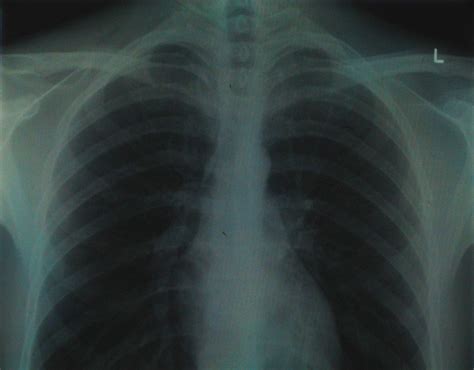

Cystic Fibrosis X Ray : Cystic Fibrosis: Posterior-Anterior Chest X-Ray | Calgary ... / For general discussion of cystic.. Pearce wilcox, md, cf clinic director, st. • respiratory causes (infection, pleural effusion, pulmonary fibrosis, intestinal lung diseases, tumors of the lung…) • cardiovascular diseases (congestive heart failure, heart valve defects…) • overwieght • abdominal causes (ascites, hepatomegaly) • psychogenic causes (hysteria). Determines the extent of lung damage, and sinus disease. Cystic fibrosis affects various organ systems in children and young adults, including the respiratory system, digestive system and reproductive system. Cystic fibrosis, also known as mucoviscidosis, is an autosomal recessive genetic disorder that affects most critically the lungs, and also the pancreas, liver, and intestine.

Pulmonary manifestations of cystic fibrosis are some of the best known in cystic fibrosis (cf). Cystic fibrosis | care guidelines for nutrition management. Your doctor may suggest genetic and sweat tests for cf if you have recurring bouts of an inflamed pancreas, nasal polyps, chronic sinus or lung infections, bronchiectasis, or male infertility. Cystic fibrosis is an inherited disease characterized by the buildup of thick, sticky mucus that can damage many of the body's organs. The disorder's most common signs and symptoms include progressive damage to the respiratory system and chronic digestive system problems. Learn more about the symptoms, causes, diagnosis, and cystic fibrosis (cf) is a genetic disorder, which means you get if from your parents at birth. It can show scarring from inflammation in the lungs. It causes changes in the electrolyte transport system.

Shows how well the lungs are able to bring oxygen in and remove carbon dioxide from the bloodstream. Paul's hospital (sph), vancouver mark chilvers md, cf clinic director, b.c. Read about the symptoms, causes and treatments. • respiratory causes (infection, pleural effusion, pulmonary fibrosis, intestinal lung diseases, tumors of the lung…) • cardiovascular diseases (congestive heart failure, heart valve defects…) • overwieght • abdominal causes (ascites, hepatomegaly) • psychogenic causes (hysteria). It affects the way your body makes mucus, a substance. This is partly because the lungs are often severely affected and the cause of significant morbidity and mortality. It is characterized by abnormal transport of chloride and sodium across an epithelium, leading to thick, viscous secretions. Cystic fibrosis (cf) is a chronic, progressive, and frequently fatal genetic (inherited) dis­ ease of the body's mucus glands. Pearce wilcox, md, cf clinic director, st. Cystic fibrosis tests may be recommended for older children and adults who weren't screened at birth. Cystic fibrosis is an inherited disease characterized by the buildup of thick, sticky mucus that can damage many of the body's organs. Learn more about the symptoms, causes, diagnosis, and cystic fibrosis (cf) is a genetic disorder, which means you get if from your parents at birth. Determines the extent of lung damage, and sinus disease.

It can show scarring from inflammation in the lungs.